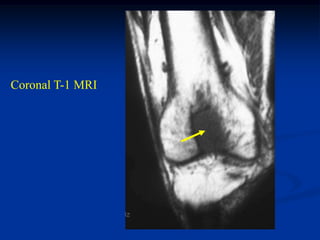

Case #1143             Metastatic Lung

73 year male with lytic lung met to the intercondylar area

Lateral view

Bone scan

Coronal T-1 MRI

Coronal T-2 MRI

Axial T-1 MRI

Sagittal T-1 MRI

Sagittal T-2 MRI

Chest x-ray showing primary lung CA